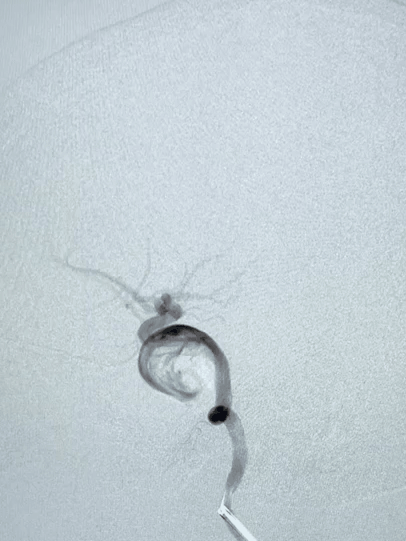

2021年1月18日,杨女士在我院神经外科收治住院,1月20日通过全脑血管造影检查,确诊为左侧颈内动脉海绵窦段巨大动脉瘤。

一个大小约28×26×26毫米的巨大动脉瘤。如葡萄般大小。

经反复沟通,家属选择多支架弹簧圈方案。杨女士于1月26日介入手术治疗。

术中,直径不到1毫米的微导管像走迷宫一样,沿着复杂的血管网络到达脑内,微导管又精确地到达动脉瘤内,填充弹簧圈成功将其栓塞。

2个小时,全神贯注,胆大心细的手术,犹如“刀锋上的芭蕾”,虽然艰难,总算顺利,动脉瘤出血的风险终于解除了。